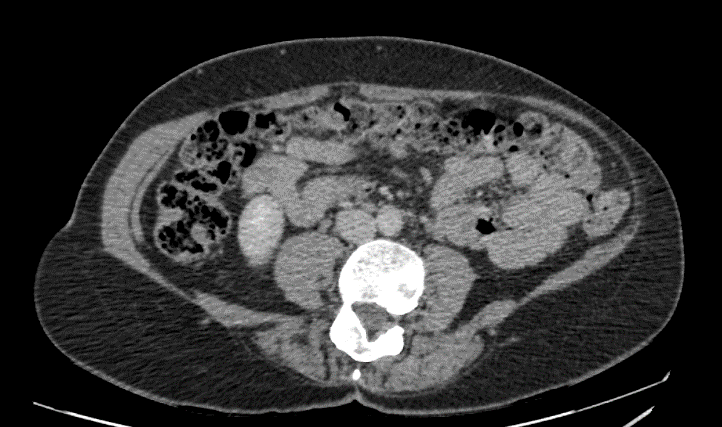

4 months later, laparoscopic left lumbar incisional hernia repair with biological mesh was carried out under general anaesthesia. A left lumbar defect which measured 18cm x 6cm was identified. The defect was closed with ten Ethibond® No 5 (Ethicon) interrupted trans fascial sutures. A laparoscopic IPOM repair was carried out using a 1.0mm thickness, 20cm x 16cm mesh formed from bovine dermal collagen matrix (Surgimend® [Integra]) which was fixed with Prolene® (Ethicon) 2/0 stays medially, laterally, and centrally. Cyanoacrylate glue (Liquiband Fix8® [Advanced Medical Solutions plc]) was used for mesh fixation to over the iliac crest, costal margin, centrally (to obliterate the dead space between mesh and peritoneum) and all other edges (Figures 2-4). There were no complications intra-operatively. Post-operatively, the patient was settled on the ward with thoracic epidural analgesia for 4 days and was discharged home 5 days after the operation.

Figure 5: CT scan transverse image performed 15 months post-operation.